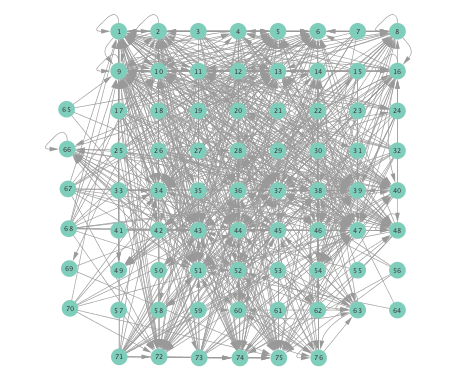

Figure 2 depicts networks inferred from different algorithms for both preictal and ictal intervals of the time series. The figure illustrates results obtained by the linear SVARM, and the K-SVARM approach with and without kernel selection. Each node in the network is representative of an electrode, and it is depicted as a circle, while the node arrangement is forced to remain consistent across the four visual representations. A cursory inspection of the visual maps reveals significant variations in connectivity patterns between ictal and preictal intervals for both models. Specifically, networks inferred via the K-SVARMs, reveal a global decrease in the number of links emanating from each node, while those inferred via the linear model depict increases and decreases in links connected to different nodes. Interestingly, the K-SVARM with kernel selection recovered most of the edges inferred by the linear and the K-SVARM using a polynomial kernel, which implies that both linear and nonlinear interactions may exist in brain networks. Clearly, one is unlikely to gain much insight only by visual inspection of the network topologies. To further analyze differences between inferred networks from both models, and to assess the potential benefits gained by adopting the novel scheme, several network topology metrics are computed and compared in the next subsection.